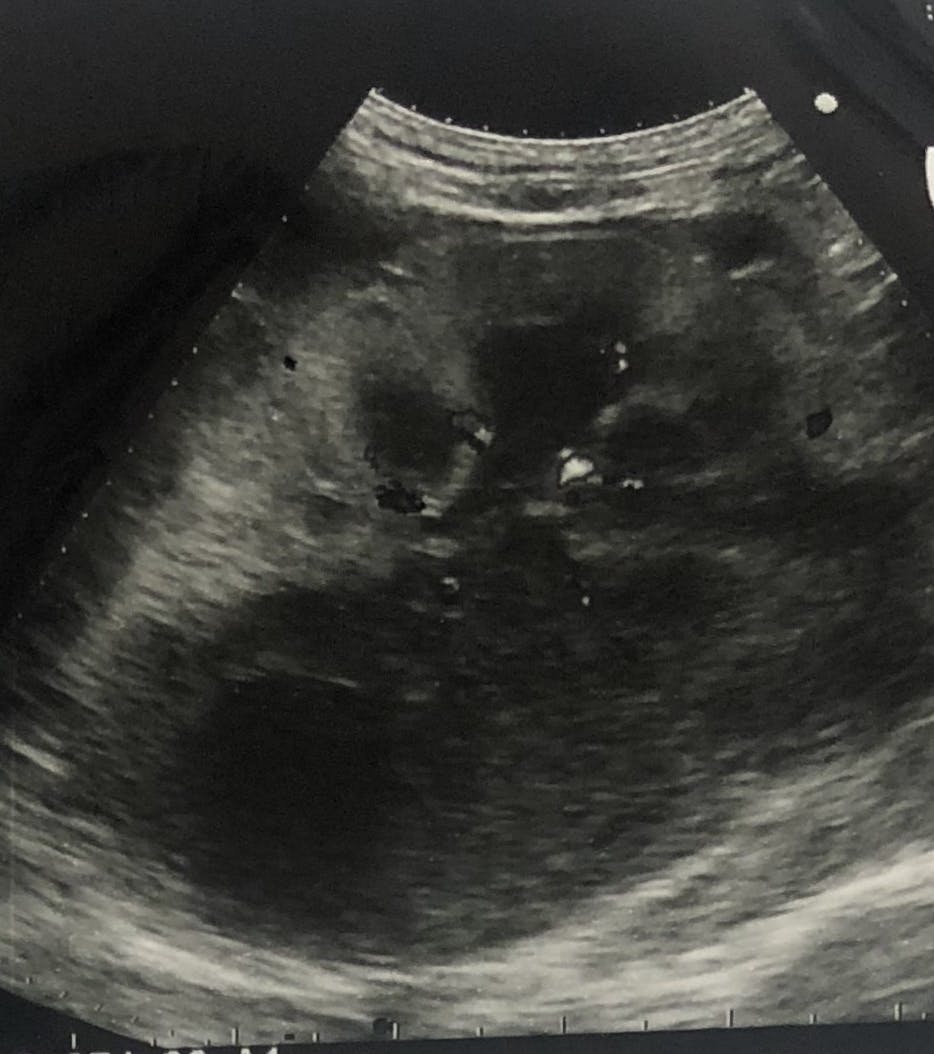

その日のうちに超音波検査、翌日CT検査を実施し膀胱に近い腸に腫瘍があるという事でした。

腎臓の超音波検査

院長先生曰く、腎臓周りも見え方がおかしいのと腸管の腫瘍からリンパ腫が疑わしいという事で、腸管の腫瘍の切除と腎臓の検査が必要と言われました。